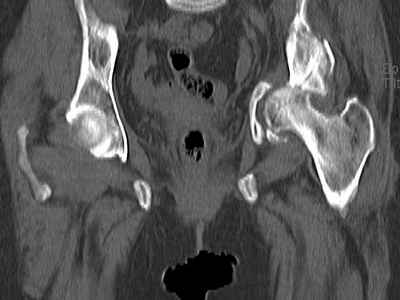

Уважаемые коллеги, возник вопрос по лечению нашей пациентки 60 лет. Около года назад множественная травма: в том числе Т-образный перелом вертлужной впадины. На сегодняшний день сращение отломков имеется на ограниченных участках, имеется дефект задней колонны вертлужной впадины. Движения неплохие, ходит с костылями, приступая на ногу. По мнению эдопротезистов при установке антипротрузионного кольца или октопуса не хватит костного материала и необходимо перед протезированием выполнить реконструкцию впадины, иначе чашка протеза неминуемо выпадет.Просьбы поделиться положительным и отрицательным опытом протезирования в подобных случаях.Возможно ли обойтись без реконструкции?Или лучше с ней?С уважением РАВ.